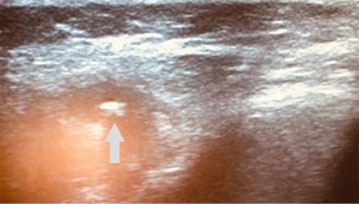

- Подводят УЗ-датчик со стороны кожи к области нахождения конкремента протока слюнной железы, определяют местоположение протока и конкремента (рис. 1).

Рис. 1. Пациент М. 28 лет, диагноз «обострение хронического калькулёзного левостороннего паротита». Конкремент в протоке околоушной слюнной железы (обозначен стрелкой)

Проведено УЗ-исследование левой околоушной слюнной железы. Результаты: структура паренхимы железы с участками понижения эхогенности без чётких границ, выводной проток неравномерно расширен от 4,5 до 7 мм в проксимальном отделе. В просвете определяется гиперэхогенная структура с нечёткими, неровными контурами до 4 мм в поперечнике с наличием акустической тени (конкремент).